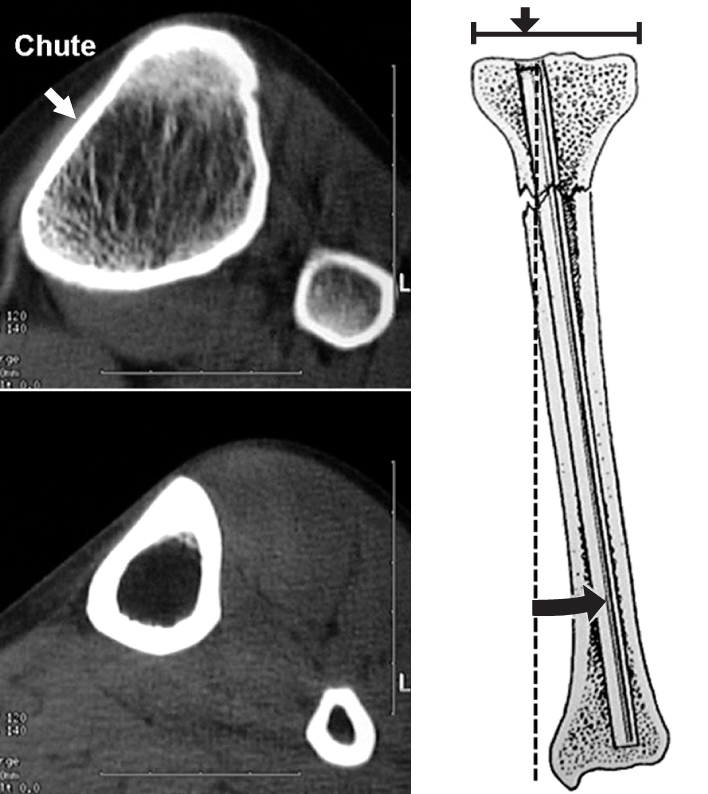

Fig. 2

The CT scan of the proximal tibia shows triangular shape of the medullary canal with most narrow medial portion. The proximal-medial portion of the tibia is a chute (white arrow) that deflects the nail laterally because of lessened sagittal space and pronounced lateral slope of the medial cortex of the proximal tibia.

Fig. 2 The CT scan of the proximal tibia shows triangular shape of the medullary canal with most narrow medial portion. The proximal-medial portion of the tibia is a chute (white arrow) that deflects the nail laterally because of lessened sagittal space and pronounced lateral slope of the medial cortex of the proximal tibia.